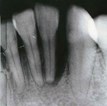

Woodland Hills, CA (PRWEB) - At his Woodland Hills cosmetic dentistry practice, Around the Corner Dental Health Spa, Dr. Kaveh Kanani is defending his patients from what former Surgeon General David Satcher called the ‘silent epidemic’ by employing the newest approach to combating gum disease. Present in eight out of ten people, signs and symptoms of gum disease often go undetected, which is why it is normally called the ‘hidden disease.’ To ensure his patients do not lose the battle against gum disease, Dr. Kanani is using the minimally invasive method known as Perio Protect® which has been confirmed to fight the bacteria that cause gum disease in a comfortable, yet effective way, killing 99.98% of the bacteria based on a study conducted by the University of Southern California.

While Dr. Kanani also offers general and restorative dentistry treatments such as dental implants in Los Angeles, he says he is doing his part to help his Around the Corner Dental Health Spa patients avoid becoming one of the tens of millions of Americans impacted by gum disease. Through the use of a personalized treatment tray, and prescription medication, Dr. Kanani is helping his patients overcome gum disease with the homecare plan. Several side effects that have been noted by patients using the Perio Protect Method™ are whiter teeth and fresher breath.